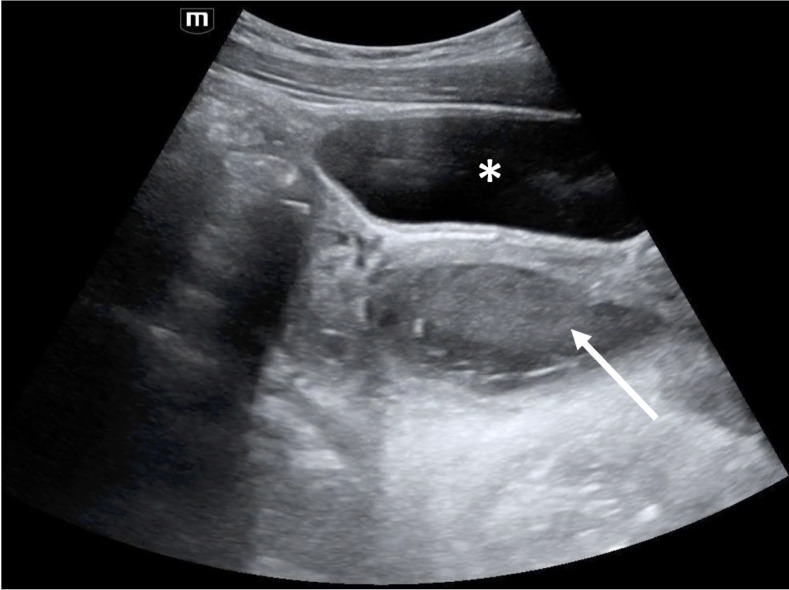

An 11-year-old postmenarchal female presented to the pediatric emergency department (ED) with 2 days of periumbilical and right lower abdominal pain. Radiology-performed ultrasound (RADUS) did not visualize the appendix, and there was a plan for surgical consultation to decide between serial abdominal exams versus computed tomography (CT) scan. While awaiting consultation and to help further narrow the differential diagnosis, the emergency provider performed a point of care ultrasound (POCUS) of the urinary tract. This revealed several anomalies including a solitary left kidney with hydronephrosis, and a well-circumscribed, fluid-filled structure with mixed echogenicity posterior to the bladder and inferior to the uterus. Given these findings on POCUS, further imaging was pursued, including a RADUS of the pelvis followed by a magnetic resonance imaging (MRI) of the abdomen. Further imaging ultimately diagnosed a bicornuate uterus, septate vagina with hematocolpos and solitary left kidney consistent with Obstructed Hemivagina and Ipsilateral Renal Anomaly (OHVIRA) syndrome. This case is an illustration of how POCUS is an invaluable tool to narrow the differential diagnosis and guide advanced imaging or consultation for both common and rare causes of pediatric abdominal pain.